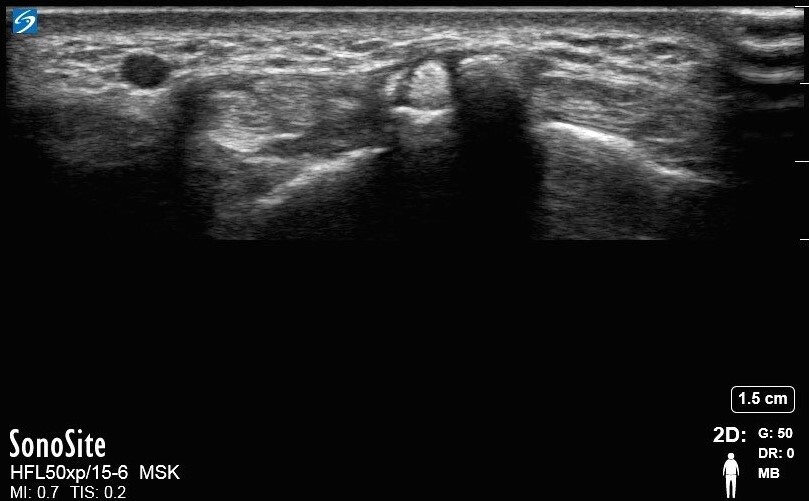

Wrist Extensor Pollicis Longus 2 Image